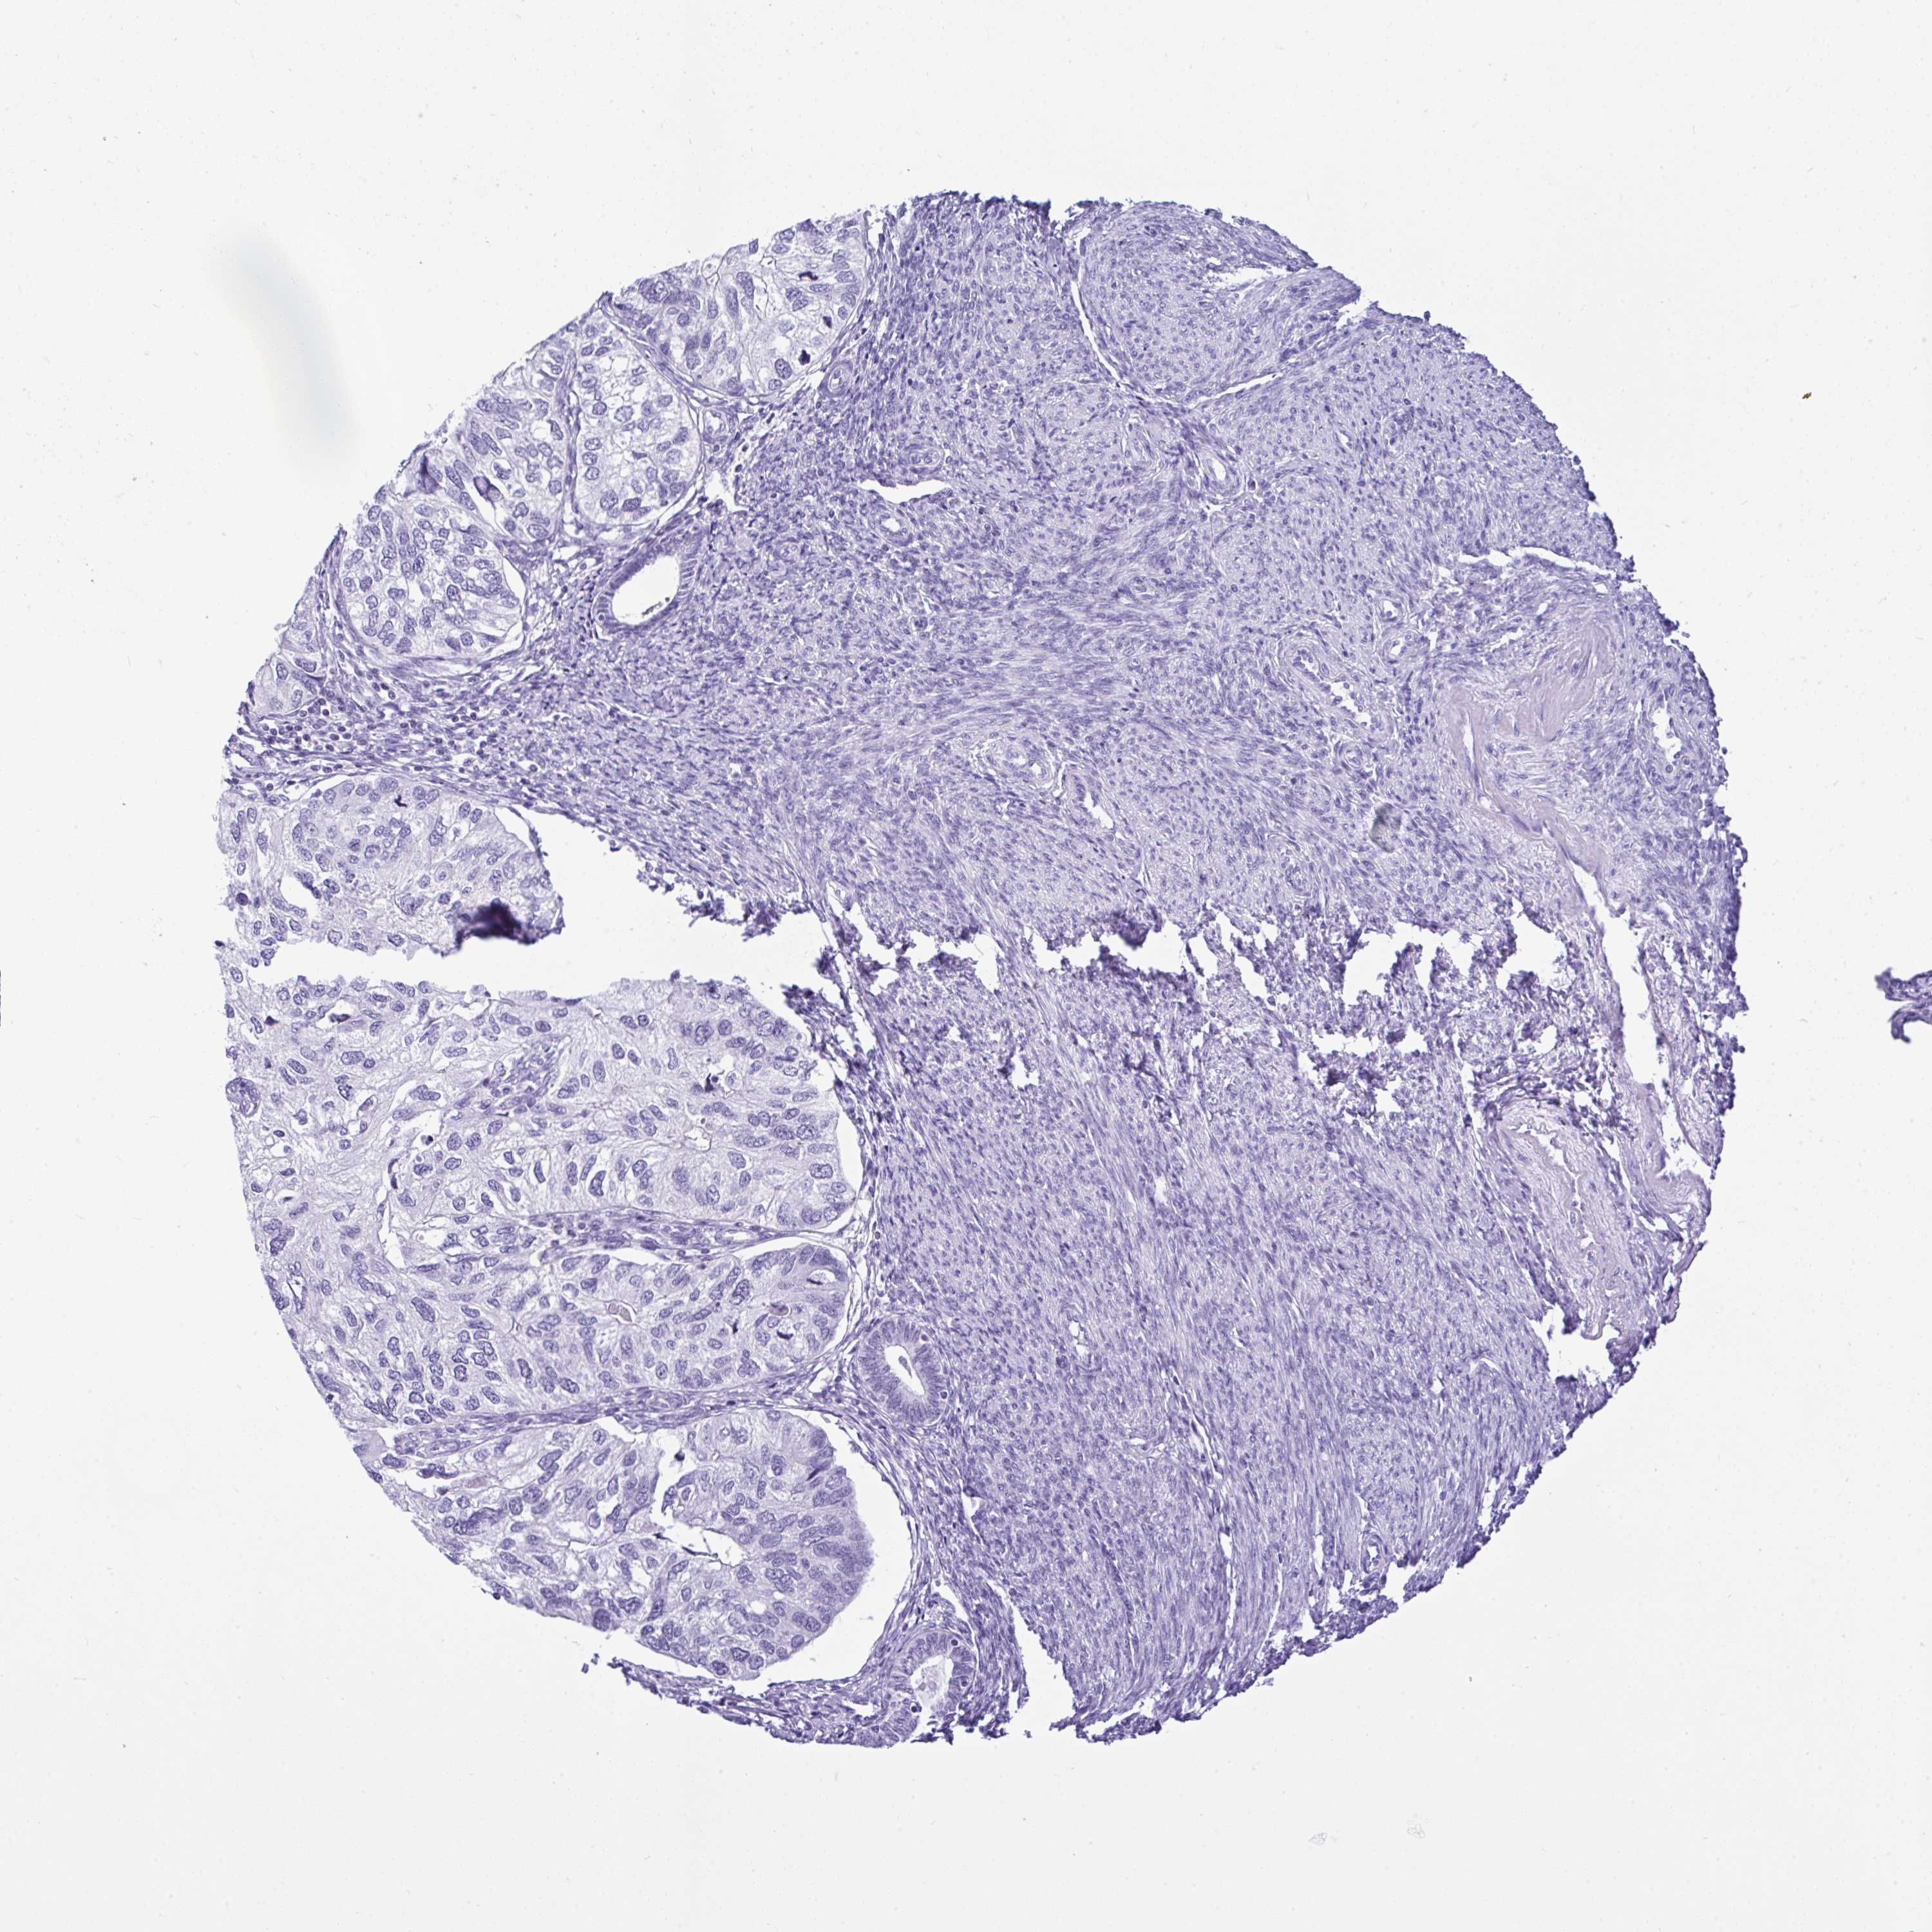

ENDOMETRIAL CANCER - Protein expressioni

A mouse-over function shows sample information and annotation data. Click on an image to view it in a full screen mode. Samples can be filtered based on level of antibody staining by selecting one or several of the following categories: high, medium, low and not detected. The assay and annotation is described here.

Note that samples used for immunohistochemistry by the Human Protein Atlas do not correspond to samples in the TCGA dataset.

Antibody stainingi

Antibody staining in the annotated cell types in the current human tissue is reported as not detected, low, medium, or high, based on conventional immunohistochemistry profiling in selected tissues. This score is based on the combination of the staining intensity and fraction of stained cells.

Each image is clickable and will lead to virtual microscopy that enables deeper exploration of all samples and also displays staining intensity scores, fraction scores and subcellular localization as well as patient and tissue information for each sample.

Antibody HPA055114

Staining

High

Medium

Low

Not detected

Intensity

Strong

Moderate

Weak

Negative

Quantity

>75%

75%-25%

<25%

None

Location

Nuclear

Cytoplasmic/membranous

Cytoplasmic/membranous,nuclear

Adenocarcinoma, NOS

Carcinoma, NOS

Adenocarcinoma, metastatic, NOS